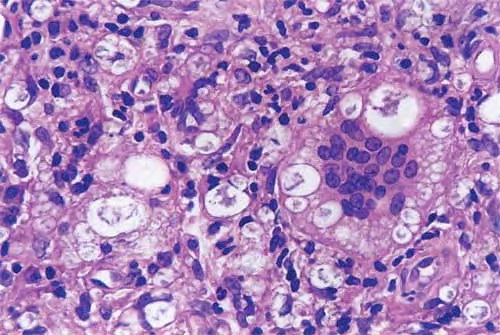

Histopathologically, the signature cell of ENL is the neutrophil, which may be abundant, scant, or absent, if an old lesion is sampled . Other common features include an increase in lymphocytes, a thickened epidermis, and a lobular panniculitis. Vasculitis is uncommon. The usual histologic pattern is a “bottom heavy” infiltrate, preferring the deep dermis and subcutis.